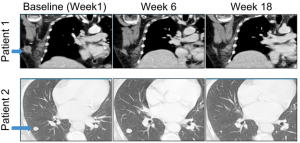

一開始,研究人員采用瘤內注射的方式,對患者進行溶瘤病毒治療。6周后,開始靜脈注射應用PD-1抑制劑。到第18周時,各期患者原發灶腫瘤及轉移灶腫瘤均有消退反應。

圖示患者原發灶及轉移灶腫瘤消退